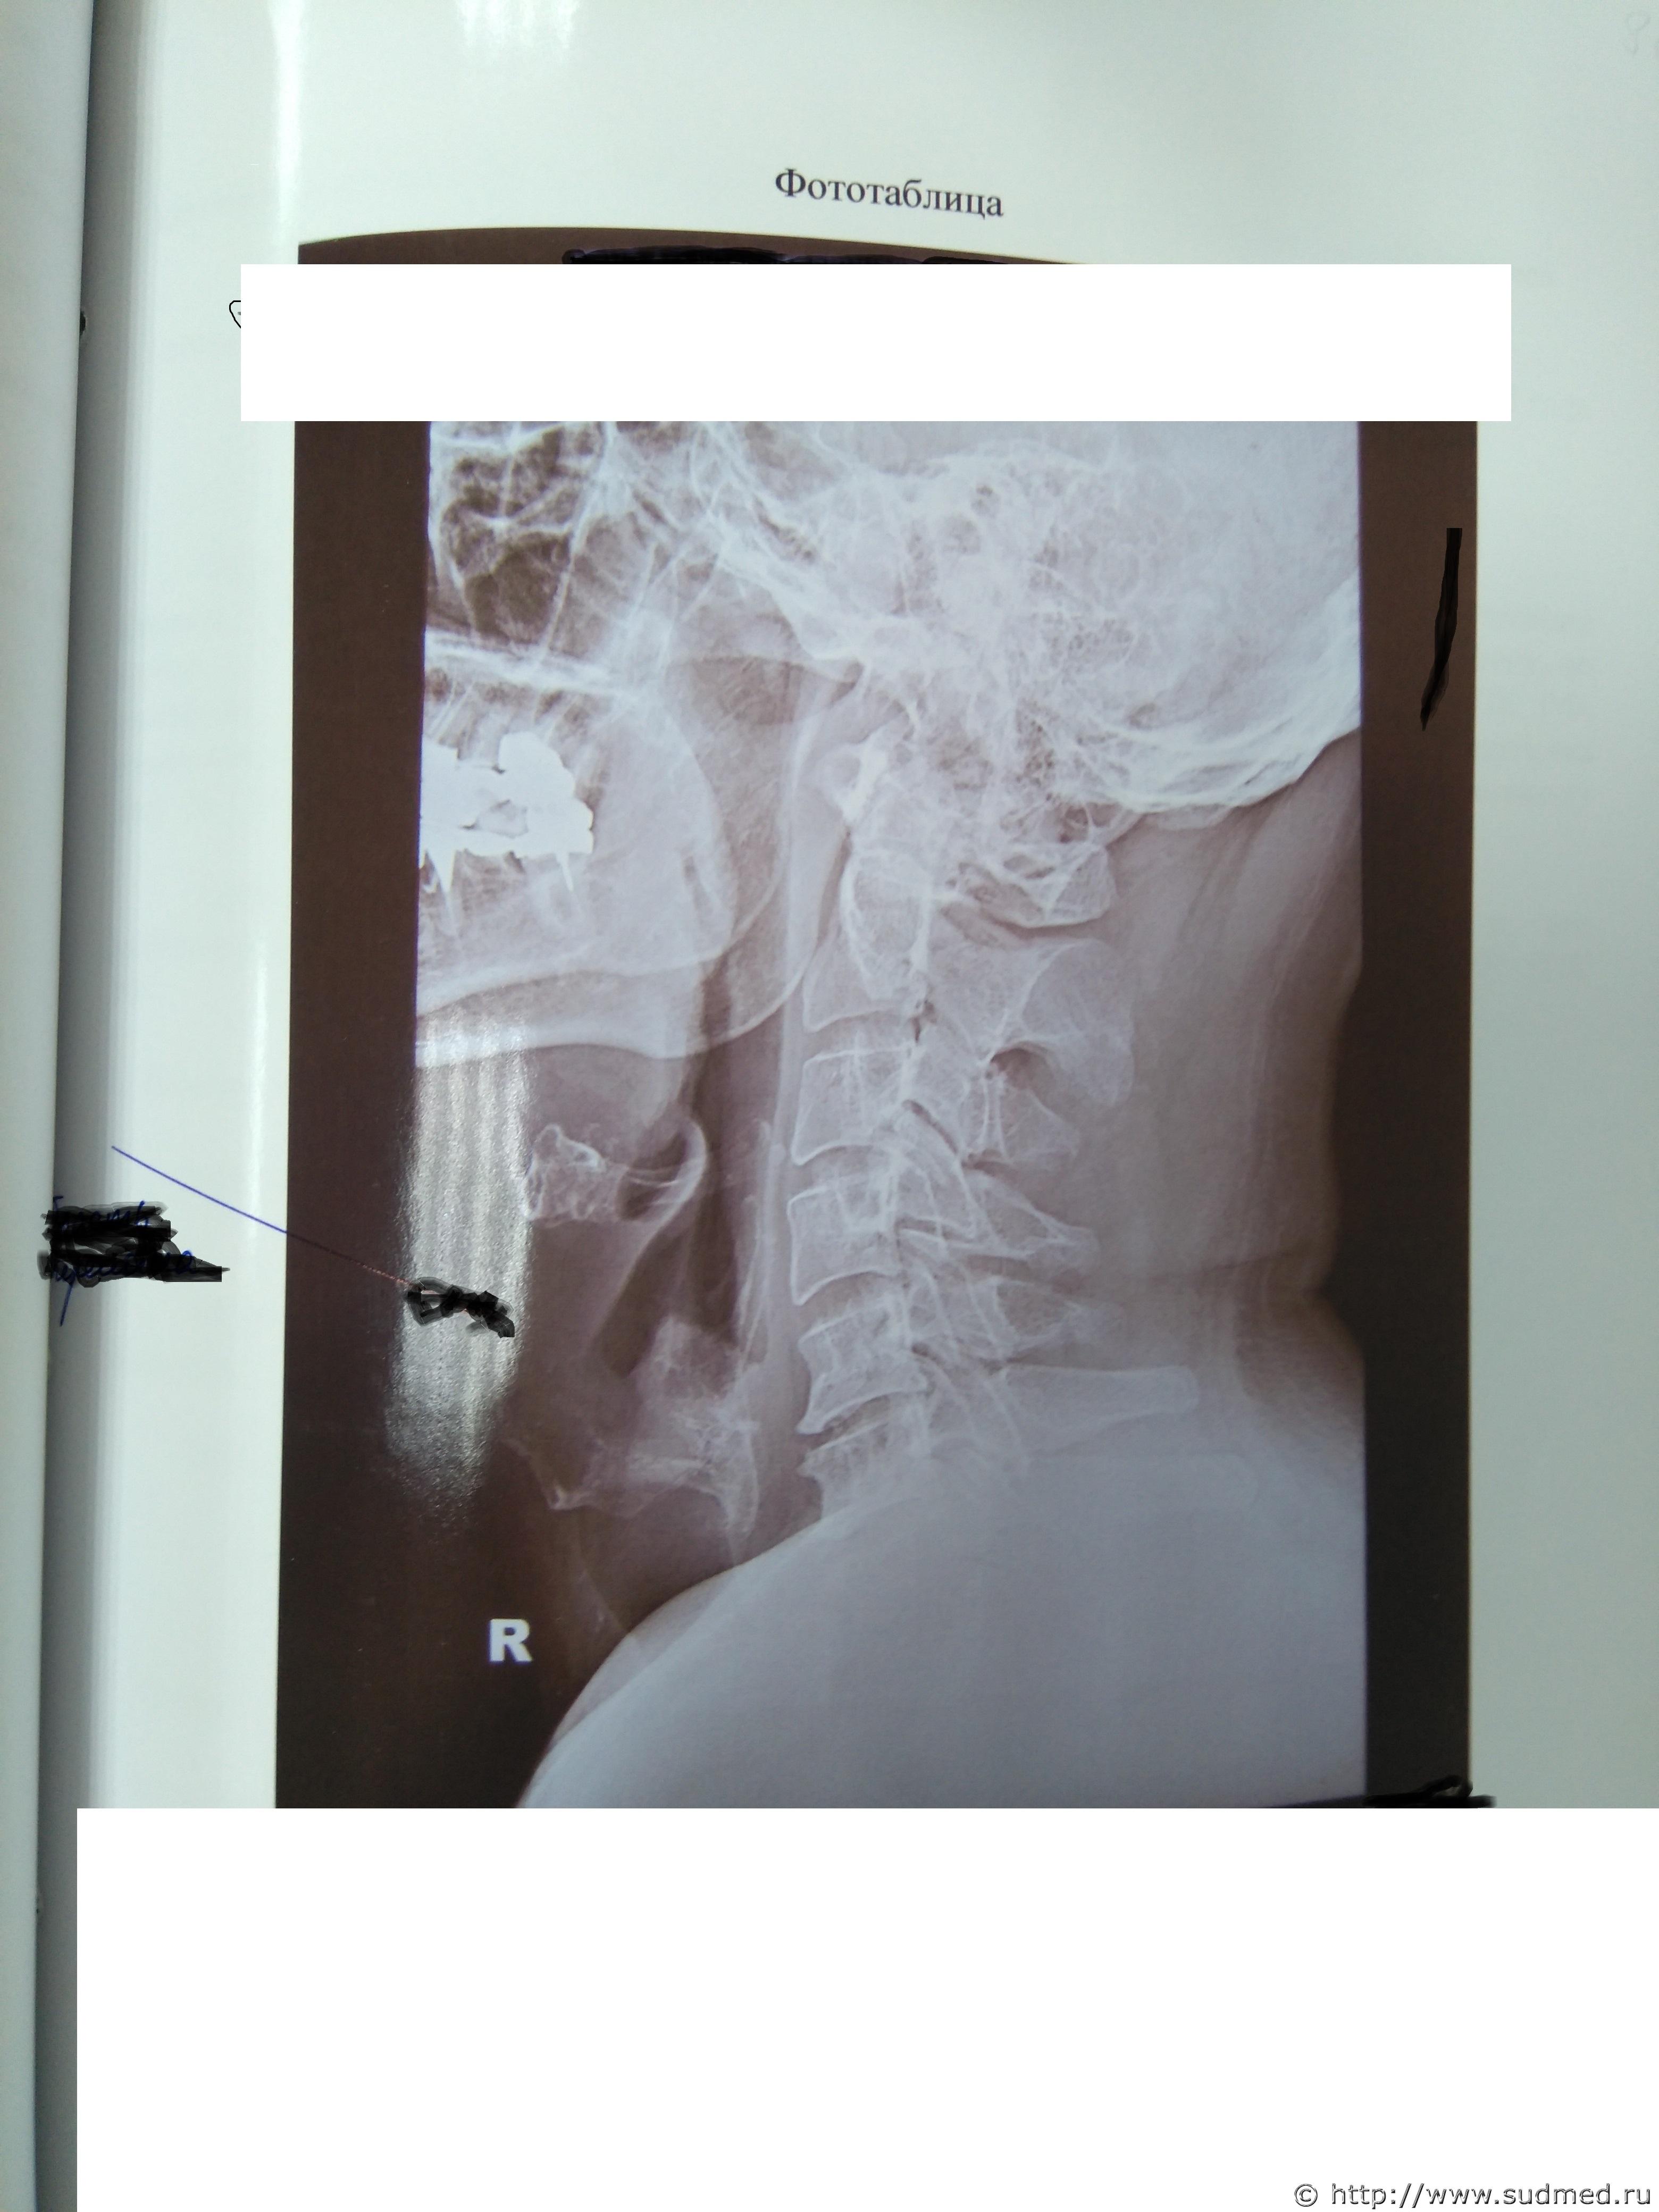

Какие повреждения видны на этой фототаблице?

Похоже на перелом щитовидного хряща, но утверждать не берусь: качество изображений низкое.

А мне кажется там компрессионный 5-6-го, либо перенесенный в анамнезе.

1. Рентгенограммы бывают разные. В первую очередь это зависит от условий съемки. Обычная цель съемки области шеи - исследование состояния шейных позвонков. В таком случае мягкие и хрящевые ткани шеи - помеха для визуализации костных структур. Маскирующее влияние этой помехи устраняется соответствующими параметрами рентгеновского исследования. Рентгеновское исследование хрящей гортани - отдельная и не очень простая задача лучевой диагностики. Не стоящая "на потоке" в лечебных учреждениях. В Вашем случае такие рентгенограммы сделаны.

Между тем врач рентгенолог на суде сказал:

1. Снимок сделан для исследования костных структур шеи. Объясняется тем, что в центре снимка находится позвоночник, а не гортань. У рентгеновского аппарата два режима, один для исследования костных структур, второй для исследования мягких тканей.

2. На рентгеновском снимке не видно щитовидного хряща. Т.е. получается как в одном фильме. Ты суслика видишь. Нет. А он здесь есть.

Кстати процитирую выдержку из атласа Кишковского: "...На снимке шейных позвонков в боковой про-

екции хорошо видны тела шейных позвонков, межпозвоночные диски, межпозвоночные суставы, остистые отростки. Четко определяются соотношения зуба 1 1 шейного позвонка и передней дуги атланта {рис. 218). По снимку могут быть реконструированы передняя и задняя стенки позвоночного ка-

нала. Снимок дает возможность оценить форму и структуру тел шейных позвонков, состояние межпозвоночных дисков, выявить дегенеративно-дистрофические их поражения. Снимок информативен при переломах и переломовывихах шейного отдела позвоночника (рис. 219), воспалительных

изменениях и аномалиях развития.